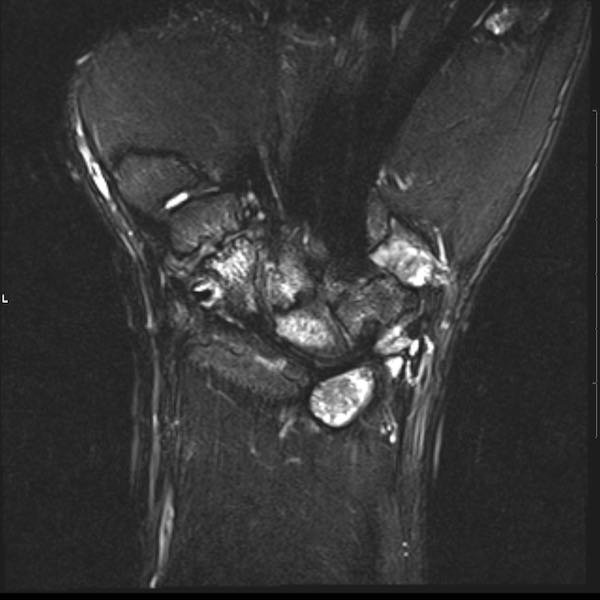

Tiếp tục xem hình ảnh MRI của bệnh nhân này.

Hình ảnh MRI:

Tràn dịch lan tỏa tất cả các khớp cổ tay.

Phù tủy xương lan tỏa tất cả các xương cổ tay.

Bào mòn xương, ví dụ tại xương thuyền, xương đầu và xương móc.

Phá hủy khe khớp và sụn khớp, rõ nhất tại khớp STT và CMC4/5.